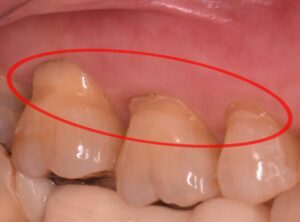

この場合、歯と歯茎の境目が欠け、神経が近くなったために知覚過敏が起こっていることがあります。

この状態は昔から「くさび状欠損」と呼ばれており、欠けた部分の形状が特徴的です。

NCCLは特に歯の頸部(歯茎に近い部分)の欠損に関連していると考えられています。

そのため、NCCL(くさび状欠損)の原因は酸蝕や摩耗など、さまざまな要因が組み合わさった多因子疾患だと考えられています。今後も、噛み合わせが関与するかどうかについては議論が続くでしょう。